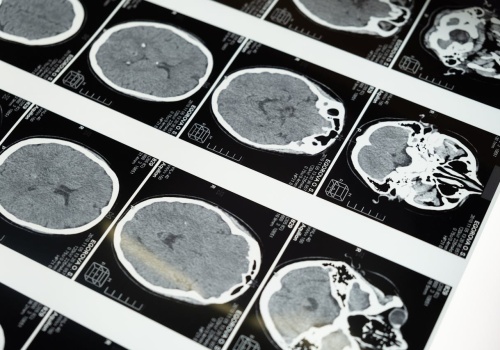

Kumulacja ołowiu w kościach może niemal trzykrotnie zwiększać ryzyko choroby Alzheimera – wynika z nowych badań. Artykuł Nowe dowody: ekspozycja na ołów zwiększa ryzyko demencji i choroby Alzheimera pochodzi z serwisu Alert Medyczny.

Tomografia komputerowa wykonana przed ciążą może zwiększać ryzyko poronienia – wynika z badania obejmującego ponad 5 mln ciąż. Artykuł Ekspozycja na promieniowanie przed ciążą może zwiększać ryzyko poronienia i wad wrodzonych pochodzi z serwisu Alert...